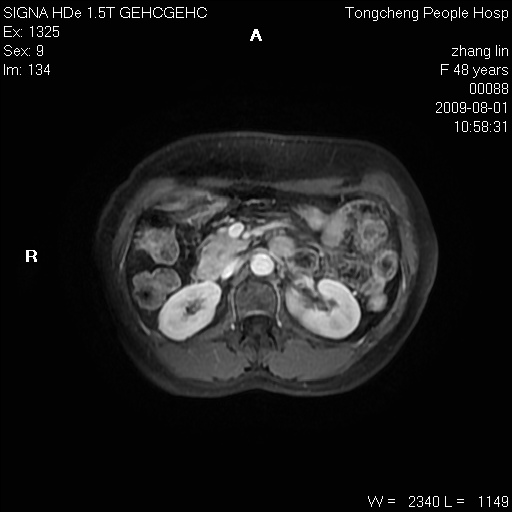

女,48岁。健康体检,彩超发现右肾占位性病变。平素健康。

临床诊断:右肾占位性病变,性质待定(囊肿?肿瘤?)。

上中腹部mr平扫+增强扫描,图像如下:

右肾上极见一类圆形病灶,t1wi呈等信号t2wi呈等高混杂信号,三期增强无强化,边界清---考虑囊肿出血。

同反相位均表现为等信号,病变无强化,考虑含蛋白的囊肿可能,弥散加权相或许有些帮助,